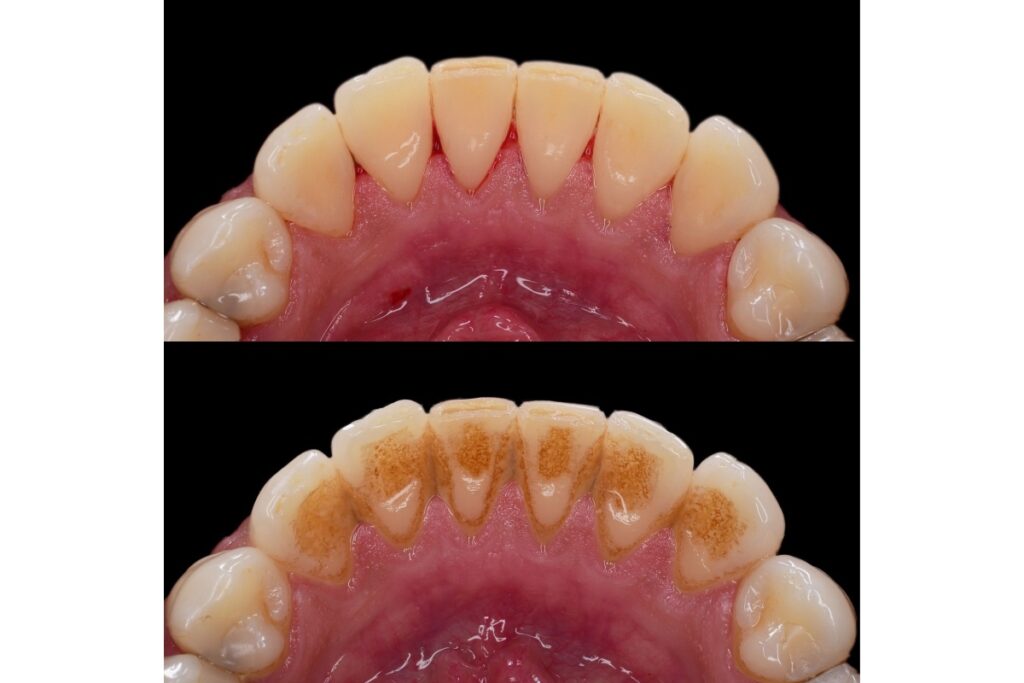

If you’ve heard your hygienist mention scaling during a regular cleaning, you might wonder how that’s different from scaling and root planing. Both procedures involve scaling (removing tartar buildup), but the key difference is where and how deep the cleaning goes:

Regular cleaning: Scaling above the gum line (supragingival scaling)

Deep cleaning: Scaling below the gum line (subgingival scaling) plus root planing to smooth tooth roots

Scaling and root planing goes much deeper than your regular cleaning. The hygienist or dentist removes tartar and bacteria from below your gum line, reaching into the pockets where gum disease develops.

The root planing part involves smoothing the surfaces of your tooth roots. This helps your gums reattach to your teeth and makes it harder for bacteria to stick to rough spots in the future.